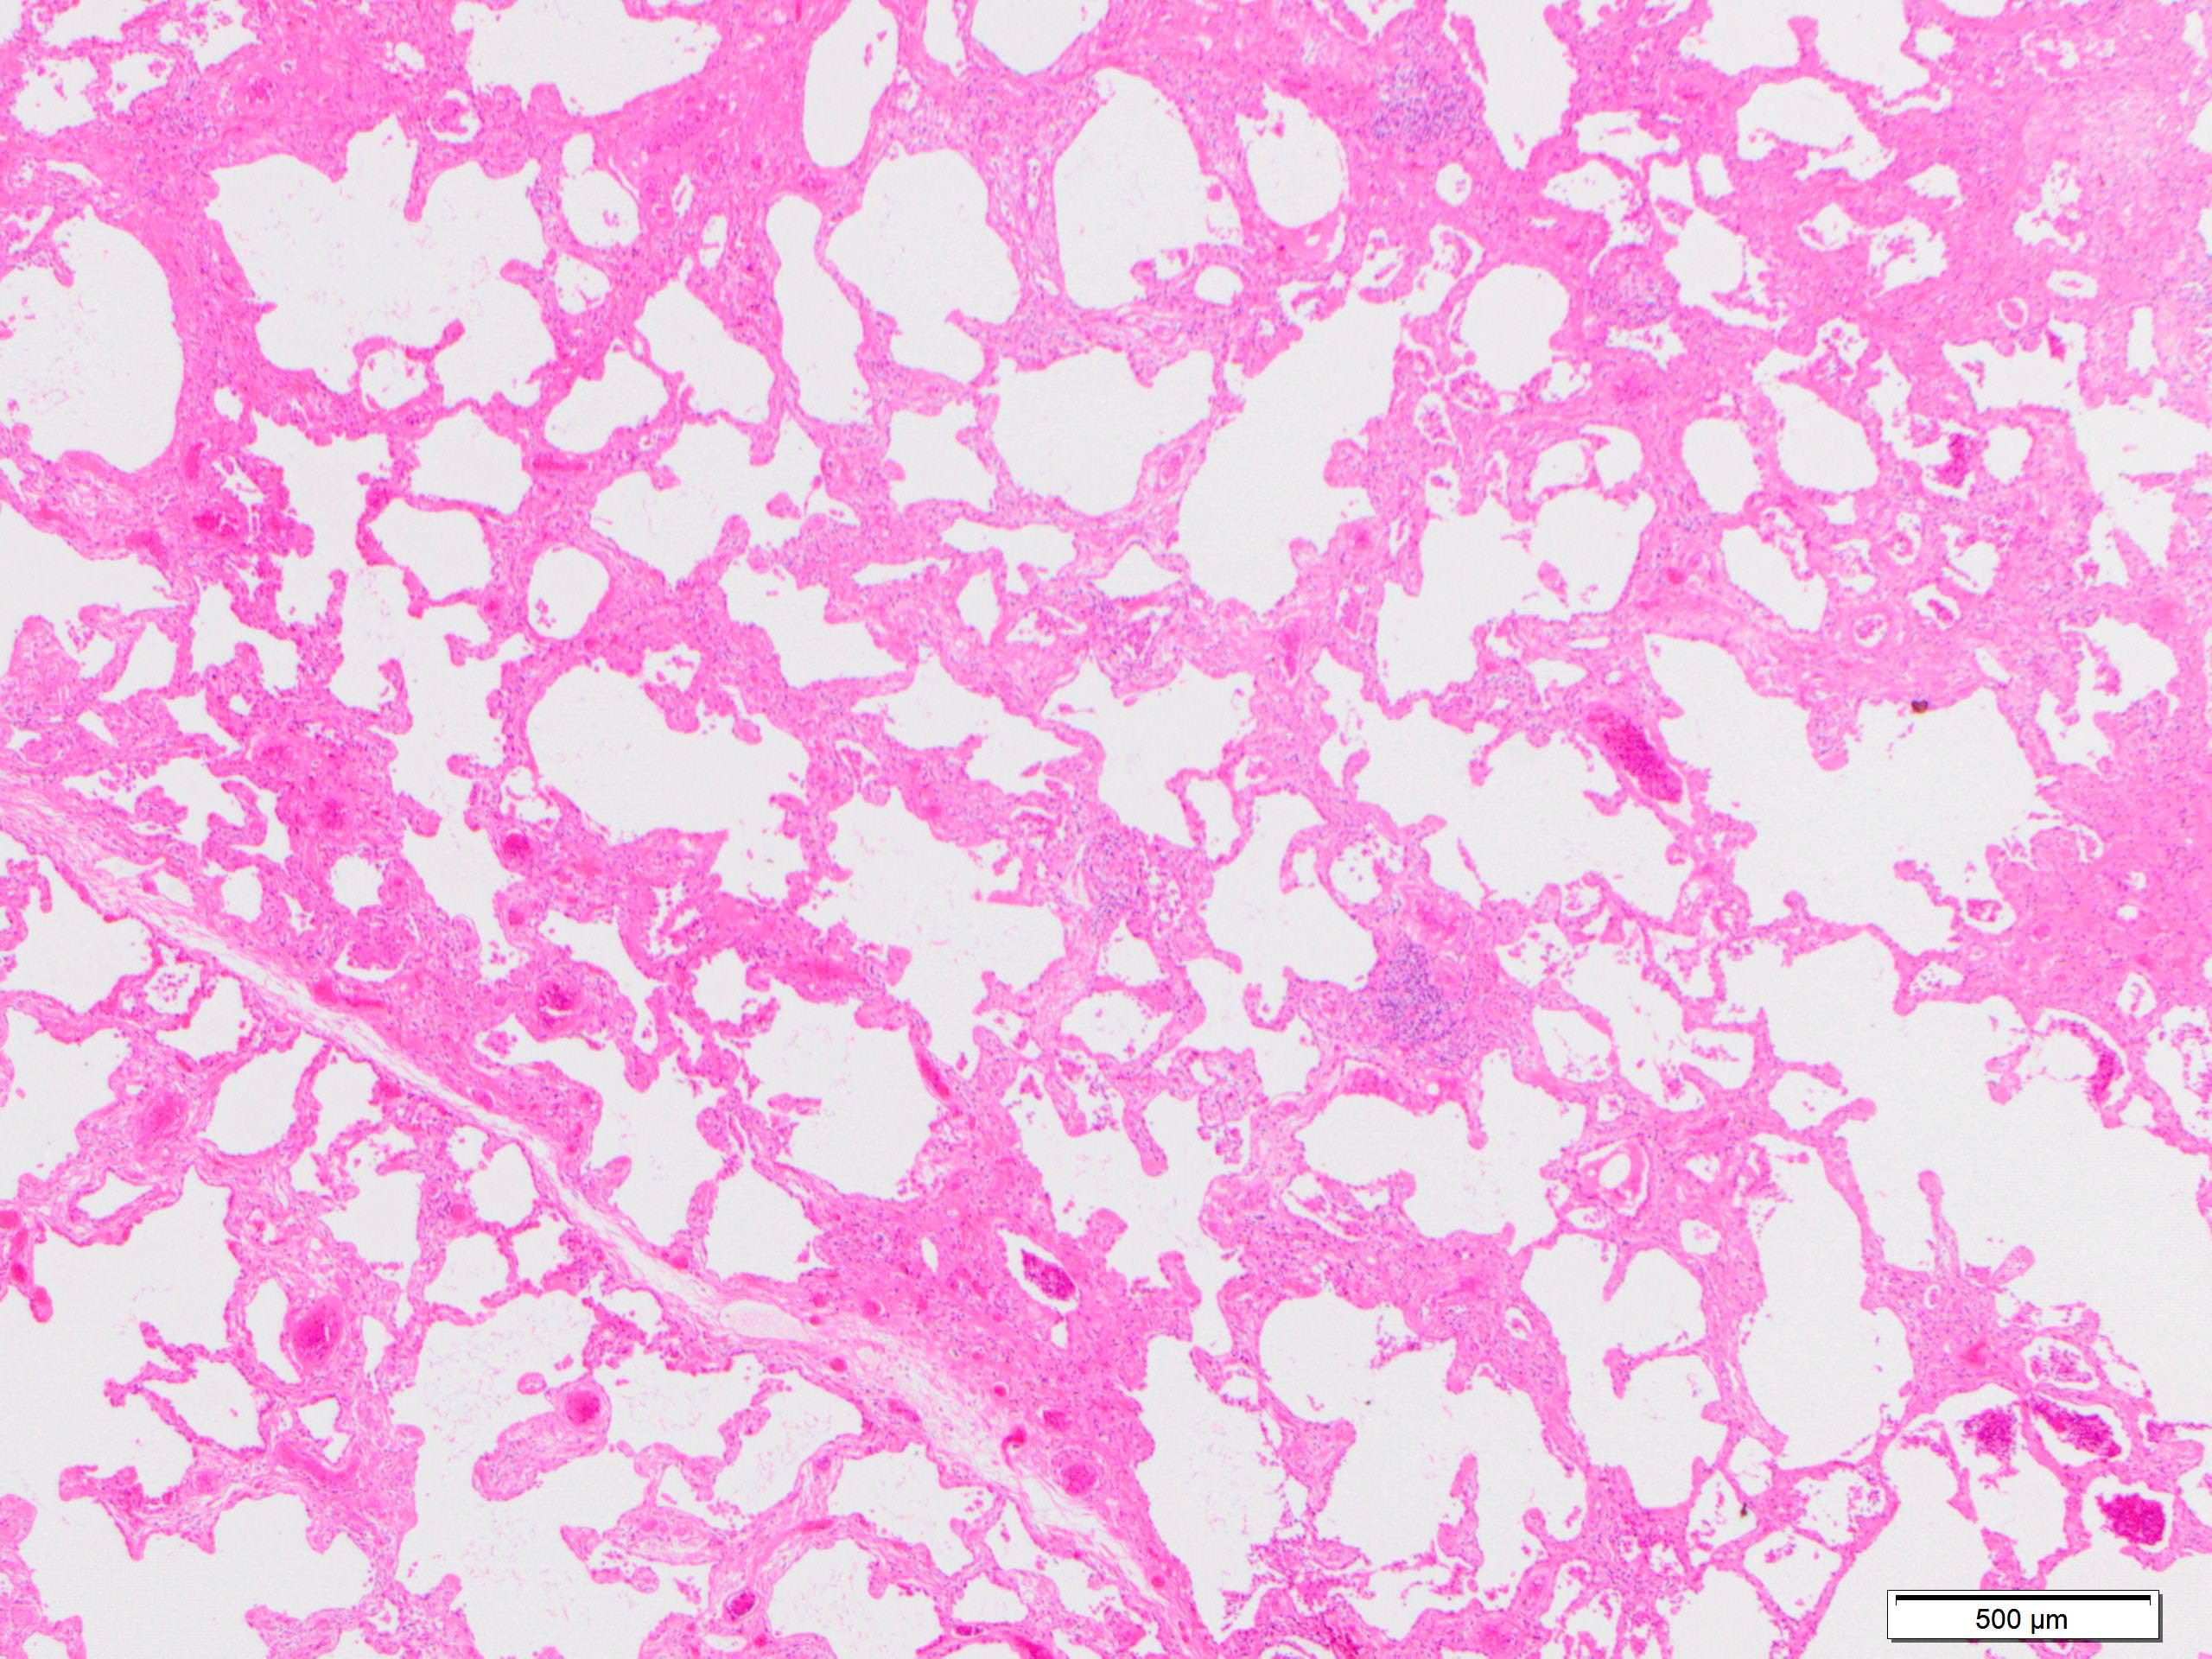

Microscopic (histologic) images

Scroll to see all images.

Contributed by Akira Yoshikawa, M.D.

- Since there are few specific findings for NSIP pattern, it is essential to exclude other lung diseases on histology (Am J Respir Crit Care Med 2008;177:1338)

- Characteristic findings of NSIP pattern

- Diffuse and uniform inflammation ("temporal homogeneity") on low power of alveolar wall, bronchovascular bundles and pleura

- There are usually no normal alveolar walls in the affected lobules

- Cellular or fibrotic change

- Lymphocytic or plasmacytic infiltration

- Loose fibrosis

- Lung architecture is frequently preserved

- "Cellular NSIP" or "fibrotic NSIP" can be stated specifically in pathologist report

- Diffuse and uniform inflammation ("temporal homogeneity") on low power of alveolar wall, bronchovascular bundles and pleura